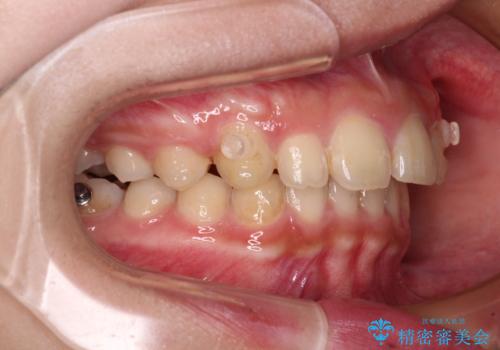

当院では通常、臼歯の咬合が理想的な位置に対して上顎が前方位にある場合。ワイヤー矯正または補助装置の併用したインビザライン矯正を選択しています。

インビザラインは、咬合力の強い方ですと、奥歯が歯肉内にめり込んでしまうため、前歯が強く接触してしまうことがあります。

こちらの方は、奥歯はしっかりと噛んだのですが、歯肉にめり込んでしまったことで、歯肉が腫れやすくなってしまいました。